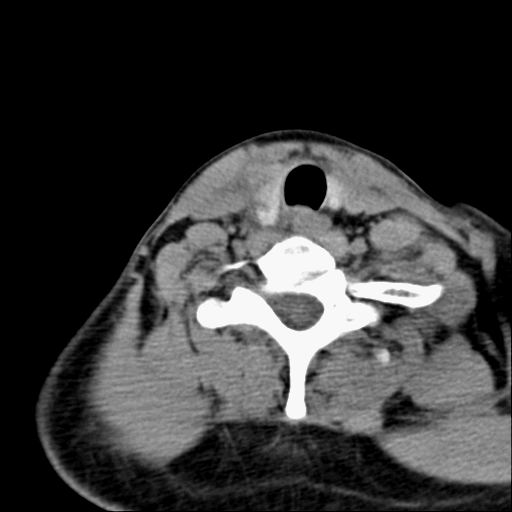

标题: CT23947 右颈部触及00.5x1.5cm质硬长形肿块,疼痛 [打印本页]

标题: CT23947 右颈部触及00.5x1.5cm质硬长形肿块,疼痛

右侧甲状腺腺瘤考虑

甲状腺癌可疑

右侧甲状腺病灶,建议增强或结合b超检查。

右甲状腺占位,建议增强。

甲状腺腺瘤或癌

甲状腺腺瘤或癌.

甲状腺右叶占位病变,建议增强扫描。

甲状腺占位  定性有时很难 但无论癌还是腺瘤 还是手术比较好!以下是甲状腺占位的ct鉴别诊断

右侧甲状腺低密度病灶,性质待定;建议行进一步检查。